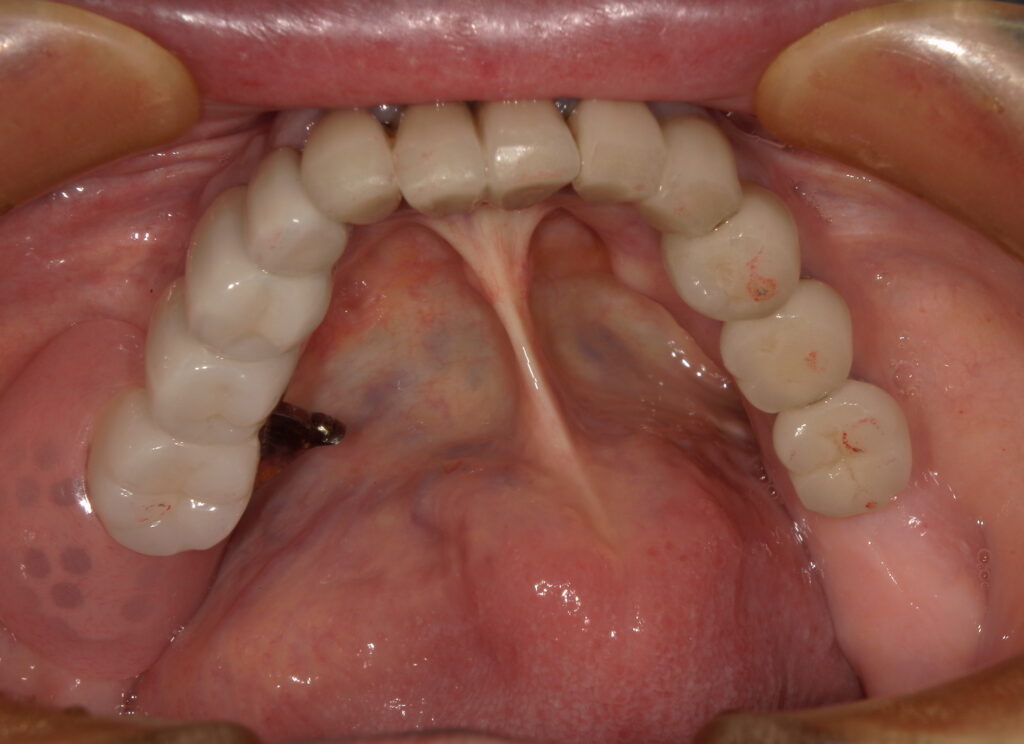

• 下顎:既存のインプラントを活かしたリーゲルテレスコープ

ドイツでは、インプラントを利用したリーゲルテレスコープは珍しい治療ではなく、「取り外しのできるブリッジ」として多く使われています。

※インプラントの土台2本

※インプラントの土台を利用して、リーゲルテレスコープを装着

※鍵を開く事で、取り外しをする事ができます。

リーゲルテレスコープ は、

✔ 取り外せる

✔ メンテナンスしやすい

✔ 修理しながら長く使える

これが大きなメリットです。